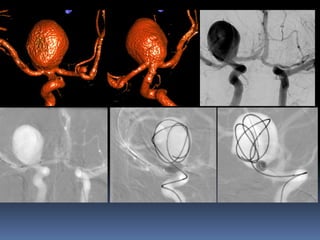

Circumferential involvement-End hole

Broad neck , dyplastic aneurysms

A

B

C

large-/giant aneurysms

Broad neck ,dyplastic aneurysms